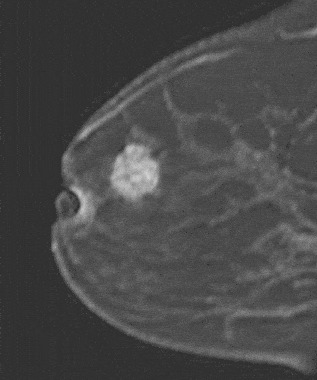

The shape and margins of masses can be described. Mass shape can be described as round (Fig. 2), oval (Fig. 3) or not otherwise specified (NOS). Margins of masses are smooth (Fig. 4), lobulated (Fig. 5), irregular (Fig. 6) or spiculated (Fig. 7). Spiculated or irregular masses are suspicious for carcinoma whereas a smooth margin is more suggestive of a benign lesion and lobulated borders are of intermediate concern. It is important to realize that margin analysis is dependent on spatial resolution and that even irregular borders can appear relatively smooth when insufficient resolution is used. Therefore, carcinoma may present with benign imaging features on MR imaging, particularly when small. In general, margin and shape analysis should be performed on the first post-contrast image to avoid washout and progressive enhancement of the surrounding breast tissue, which could obscure lesion analysis.

Figure 4. Smooth lobulated mass. Pathology – Fibroadenoma.